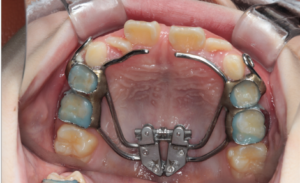

Before |

治療途中の小児矯正の症例です。あごの成長を利用しながら、拡大装置で歯が並ぶスペースを広げ、

マウスピース矯正で歯の位置を少しずつ整えています。

Before